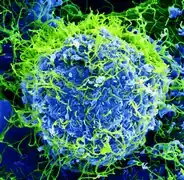

Medicine has been practiced since prehistoric times, and for most of this time it was an art (an area of creativity and skill), frequently having connections to the religious and philosophical beliefs of local culture. For example, a medicine man would apply herbs and say prayers for healing, or an ancient philosopher and physician would apply bloodletting according to the theories of humorism. In recent centuries, since the advent of modern science, most medicine has become a combination of art and science (both basic and applied, under the umbrella of medical science). For example, while stitching technique for sutures is an art learned through practice, knowledge of what happens at the cellular and molecular level in the tissues being stitched arises through science.

Selected image –

General images –